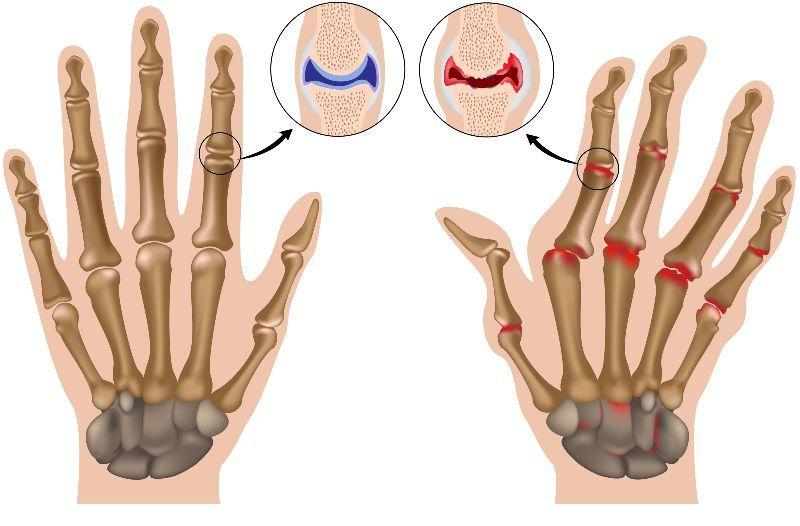

类风湿关节炎滑膜改变

【筋骨堂】手指关节疼痛,变形是骨关节炎还是类风湿?